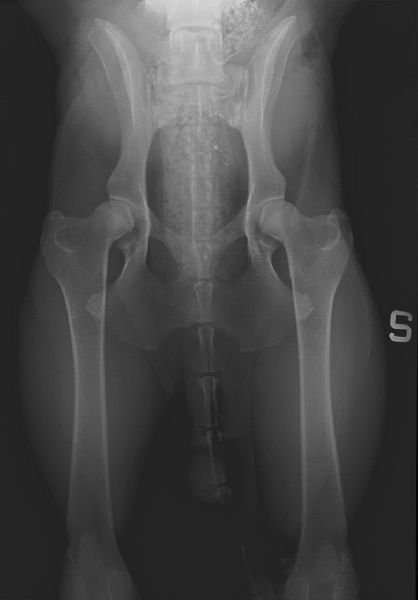

MATISSE des Gardiens de Rome ( Esente da Displasia HD A - ED 0 )

MATISSE des Gardiens de Rome (radiografie anche e gomiti del 31/07/12)